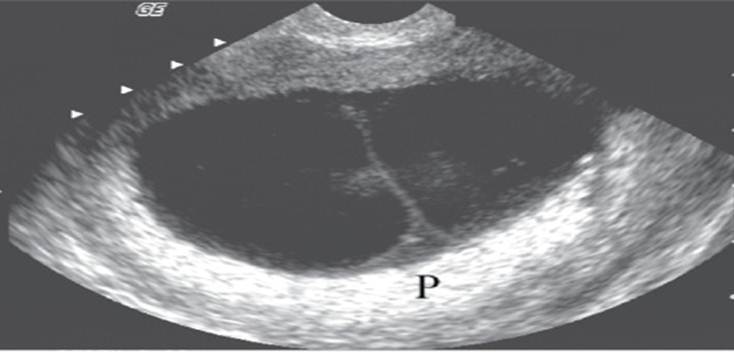

pleural fluid

ascites

Placenta previa